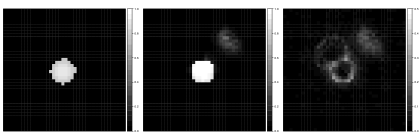

It may occur in practice that multiple reference atlases are subject to the same deleterious effect, resulting in multiple atlases closely agreeing on an incorrect segmentation. If we have one atlas that registered well and provides a good segmentation, it could still be outweighed by multiple poor atlases. Thus any voting procedure would produce a poor segmentation.

We again simulate a structure on a grid, displayed in Figure 4. Also displayed in the figure is one reliable candidate segmentation and three poor segmentations, the latter of which closely agree. We also simulate image intensities as might be obtained from an additional imaging modality. Voxelwise image intensity similarity is often used to quantify rater reliability throughout an image (Isgum et al., 2009). As such, we simulate image intensity similarities for each atlas, displayed in Supplementary Figure 1. To make the assessment more realistic, we slightly offset the intensity differences from the areas of poor segmentations.

Figure 5 displays the posterior mean estimate of the target along with pixel-wise standard deviations. To reduce the Monte Carlo variance, we use “Rao-Blackwellized” estimators, , where denotes the MCMC iterate of all the parameters except . Close agreement between the target and the estimate is evident. As expected, the uncertainty about the structure is largest near the edges of the observed segmentations, as well as in the area of higher intensity. The effect of high intensity is strongly attenuated when it is thought to be well away from the target object. Posterior inference also produces estimates of the reliabilities of the rater atlases. Supplementary Figure 3 displays the estimated sensitivity and specificity fields for each of the four atlas segmentations. We see that all atlases have high specificity in regions well away from the structure. Near the object, however, we observe high sensitivity of the good atlas with lower values for the poor ones. Conversely, the tendencies for the bad atlases to produce false positives are seen in the areas of low specificity.

Most existing label fusion procedures result in a binary map corresponding to inclusion/exclusion of voxels in a structure of interest. Thresholding the posterior probability maps at 0.5 also yields such a binary map, displayed in Figure 6. For comparison, the figure also displays the segmentations that result from simple majority voting, globally-weighted majority voting (Artaechevarria et al., 2008) in which each atlas is weighted by the inverse of its average squared intensity difference, and locally-weighted majority voting (Artaechevarria et al., 2009) in which the contribution of each atlas at each pixel is weighted by the inverse squared intensity difference from the target. We can see the superior recovery of the target under our approach versus different versions of majority voting. The figure also gives the Dice similarity coefficients quantifying similarity between each segmentation and the target, where the target is dichotomized to zero / non-zero pixels. Let denote the indicator of inclusion of pixel in the estimated image. The Dice coefficient, calculated as , is often used as a measure of image similarity (though it may not be the best measure when the structure of interest is small relative to the image size (Taha and Hanbury, 2015)). Dice values close to one indicate strong agreement between two images. Despite the fact that all of the poor segmentations were downweighted relative to the good one, they still outweigh the quality atlas in each voting procedure, resulting in poor segmentation. Thresholding the posterior probability map has resulted in improvement in similarity over even the most favorable version of majority voting.